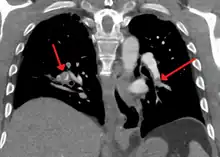

On CT scan, pulmonary emboli can be classified according to level along the arterial tree.

Segmental and subsegmental pulmonary emboli on both sides